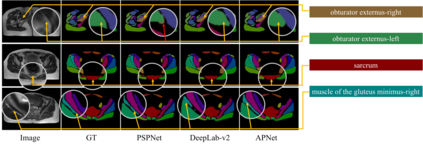

One of the time-consuming routine work for a radiologist is to discern anatomical structures from tomographic images. For assisting radiologists, this paper develops an automatic segmentation method for pelvic magnetic resonance (MR) images. The task has three major challenges 1) A pelvic organ can have various sizes and shapes depending on the axial image, which requires local contexts to segment correctly. 2) Different organs often have quite similar appearance in MR images, which requires global context to segment. 3) The number of available annotated images are very small to use the latest segmentation algorithms. To address the challenges, we propose a novel convolutional neural network called Attention-Pyramid network (APNet) that effectively exploits both local and global contexts, in addition to a data-augmentation technique that is particularly effective for MR images. In order to evaluate our method, we construct fine-grained (50 pelvic organs) MR image segmentation dataset, and experimentally confirm the superior performance of our techniques over the state-of-the-art image segmentation methods.